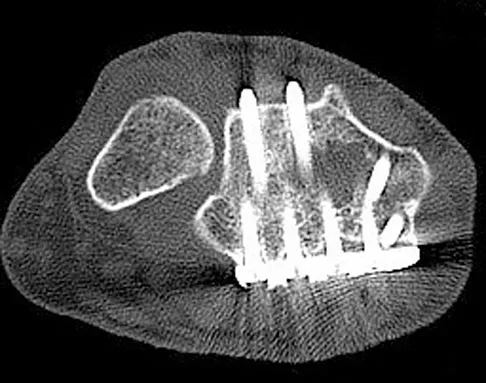

A patient is treated with volar plating for a distal radius fracture. The CT scan shown in Figure 15 is obtained after union of the fracture because the patient reports ongoing symptoms. The prominent hardware is most likely injuring what tendon?

Explanation